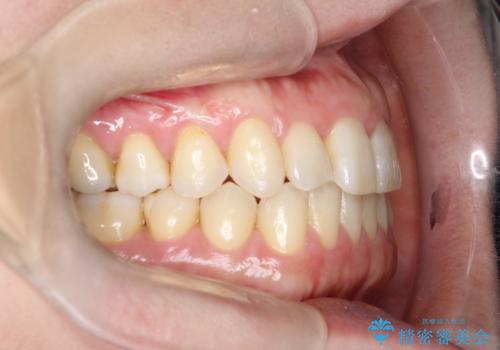

上の歯と下の歯が反対にかんでいる インビザラインによる目立たない矯正

- 右上の前から2番目と3番目の歯が内側に引っ込んでしまっているのを主訴に来院されました。

右上の2番目と3番目のはが前後反対にかんでしまっている状態でした。

インビザラインにて治療することとしました。

内側に引っ込んでいる歯も、インビザラインにてしっかり外側に動かすことができます。